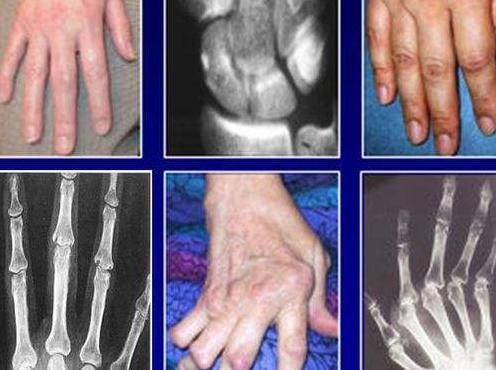

类风湿性关节炎具有隐匿性高、难确诊、受损不可逆和致残率高等特点。它可以发病于身体的任何一个关节,常发病于指、掌、腕部小关节。

据调查研究表明,隐匿型类风湿性关节炎患者占类风湿关节炎病人总数的60-70%。缓慢起病,常于数周或数月内逐渐起病,表现为掌指关节和腕关节的疼痛、肿胀和僵硬,可伴全身不适和乏力、低热、食欲不振、体重下降等。

2、经过数周或数月后出现关节疼痛、肿胀,往往从一个或几个关节受累,常首先累及大关节,在一段时间内病变局限于该关节,逐渐发展到数个、十几个或数十个关节受累,终可扩散到腕、指、踝、趾等多个关节,呈两则肢体关节的对称性分布。